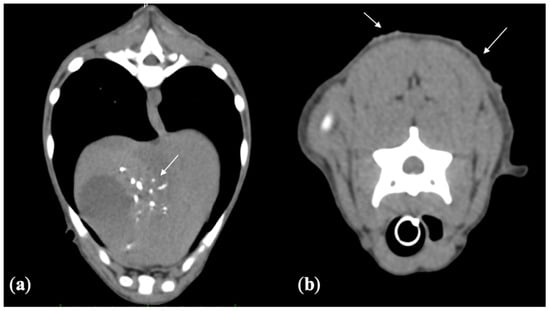

2.4.1. Computed Tomography